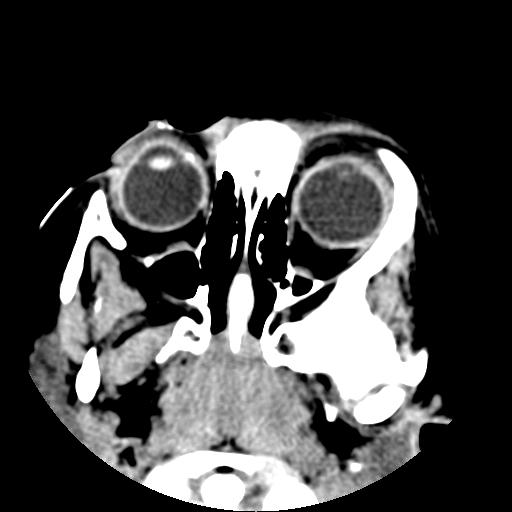

以下是引用深泽交通医院在2009-10-16 8:25:00的发言:[br]右眼环出血伴异物

以下是引用卜一在2009-10-16 15:01:00的发言:[br]右眼球挫裂伤伴异物!

以下是引用拾荒者在2009-10-17 18:38:00的发言:[br]鼻面部皮下积气,右侧睑缘及眼球壁高密度异物影,左侧眼球壁晶状体内侧缘处是圆形低密度影。低密度异物?应提请眼科医生注意。